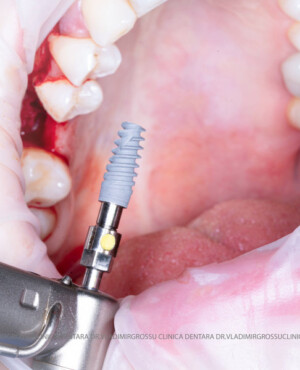

Cele mai utilizate patru categorii de materiale, în funcție de origine, sunt:

- Autogrefe — os propriu, recoltat de la pacient;

- Alogrefe — os uman prelucrat, recoltat de la donatori vii sau decedați;

- Xenogrefe — os de origine bovină;

- Materiale osteoplastice sintetice — cu avantaje și limitări specifice.